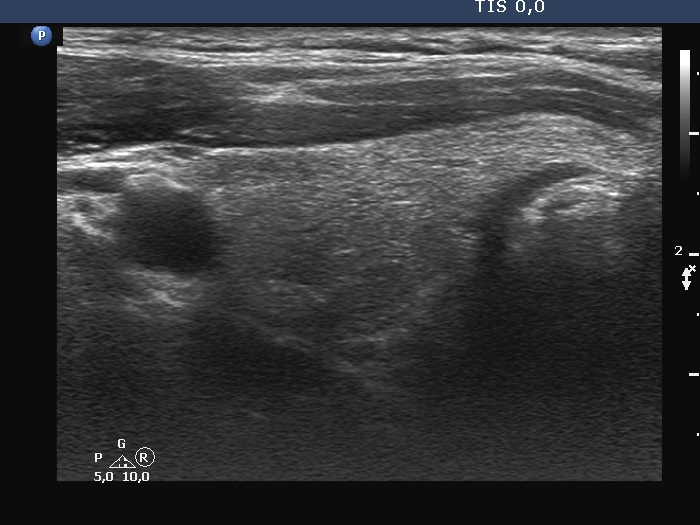

Examination 7 months later (second row of images):

Clinical presentation: The patient became asymptomatic within 12 hours after the first dose of methyl-prednisone and remained so.

Palpation: no abnormality.

Laboratory tests: TSH 1.03 mIU/L, FT4 14.2 pM/L, CRP 0.7 mg/L.

Ultrasonography: Both the size of the nodule and the extent of hypoechoic areas have decreased. An isoechoic nodule has appeared which was obscured by hypoechogenicity in the previous study. The vascularity was still very scanty.

Suggestion. Follow-up in 2 years.